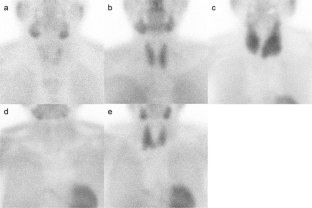

Fig. 2